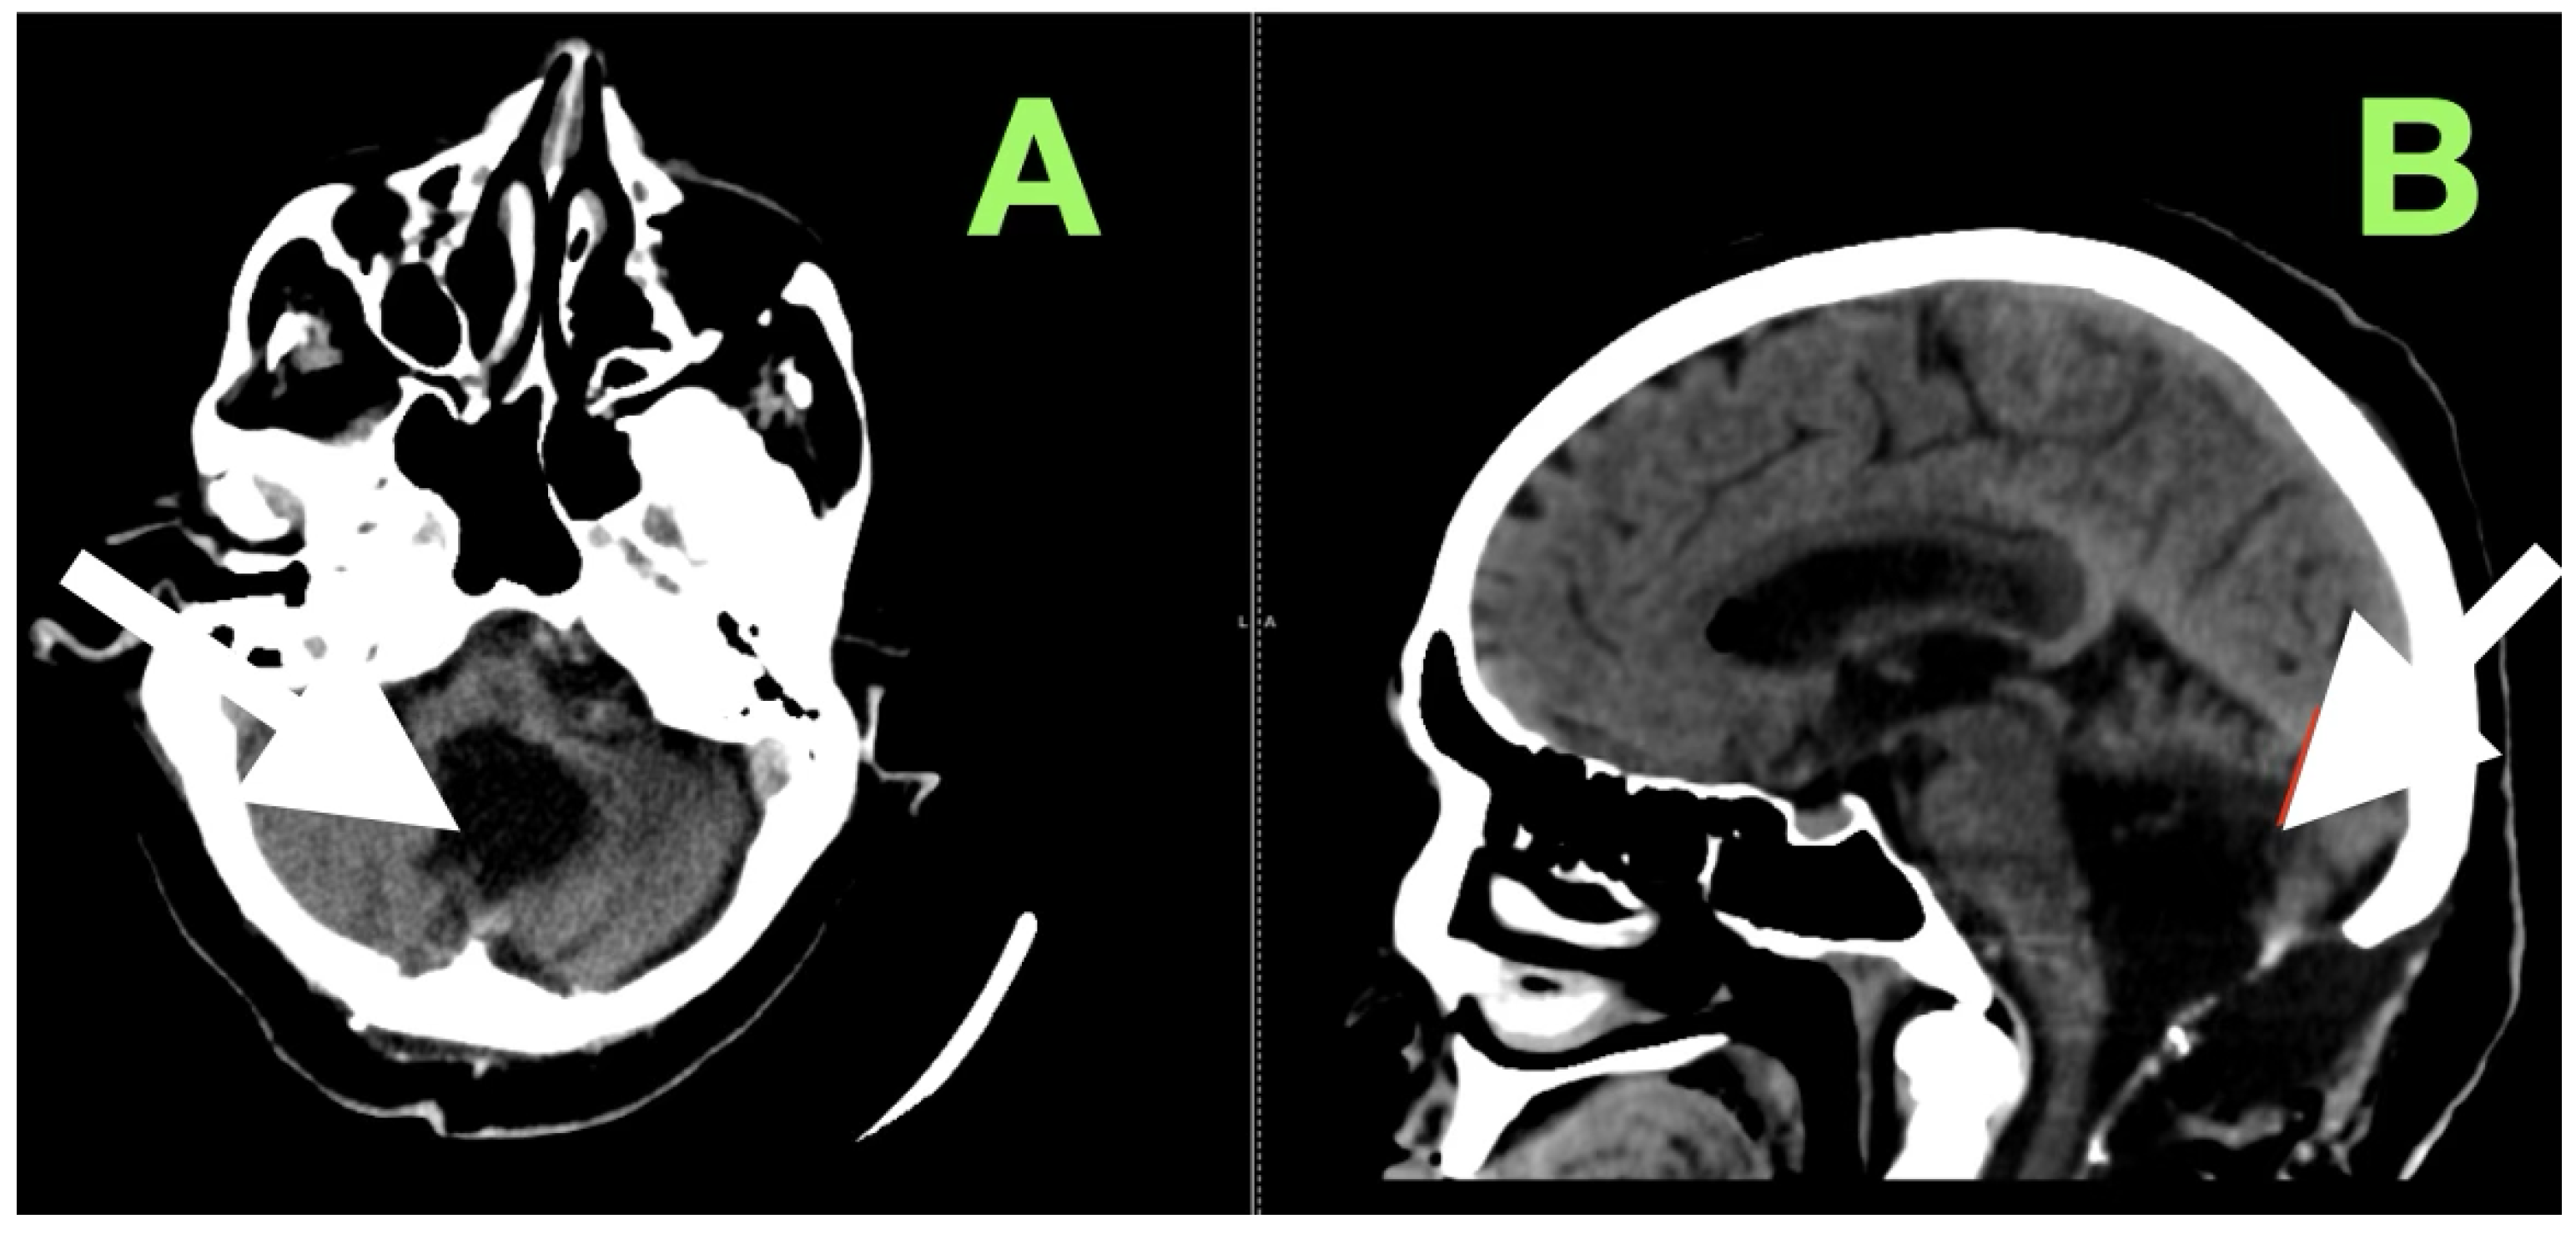

Axial T2-weighted sequences (Figure 2A,B) revealed a large, lobulated mass occupying most of the left cerebellar hemisphere, insinuating between folia and extending across the midline into the inferior vermis. The lesion was markedly hyperintense compared to cerebellar parenchyma, with internal heterogeneity suggesting layered keratinaceous content. The inferior pole of the mass descended into the cisterna magna, and its medial aspect encroached on the fourth ventricle, partially effacing it and displacing its floor anteriorly over the dorsal medulla. This displacement explained the patient’s severe truncal instability, as vermian compression interrupts integration of proprioceptive and vestibular input, and also her left-sided appendicular ataxia, arising from disruption of cerebellar hemispheric coordination pathways projecting through the dentate nucleus and superior cerebellar peduncle.

Susceptibility-weighted imaging (Figure 2C) showed tiny punctate hypointense lesions foci within lesions, suggestive of microcalcifications or hemosiderin secondary to chronic contact with the tentorium, vasculature, and pia, all indicating a long-standing, slowly growing mass. Post-contrast T1-weighted imaging (Figure 2D) displayed no enhancement, considering both lesions were different from a meningioma, hemangioblastoma, or metastasis. Coronal T2-weighted sequences (Figure 2E) demonstrated inferior and lateral extension to the foramina of Luschka, stenosing the lateral recesses of the fourth ventricle and displacing the cerebellar peduncles, most notably left. This accounted for the gaze-evoked nystagmus and pursuit deficits, considering vestibulocerebellar input and flocculonodular output. Cerebellomedullary junctional contact was responsible for the subtle bulbar discoordination secondary to pressure to the dorsal medulla near the nucleus ambiguus. Sagittal FLAIR (Figure 2F) showed an anteriorly displaced brainstem; however, the dorsal medulla was compressed against the wall of the fourth ventricle, with the pontomedullary junction displaced anteriorly. The prepontine cistern was partly effaced, and the basal cisterns were narrowed but still patent; however, inferior edema was enough for acute obstructive hydrocephalus.

Figure 2. Preoperative magnetic resonance imaging of the posterior fossa. (A,B) Axial T2-weighted images reveal a large lobulated hyperintense lesion occupying the left cerebellar hemisphere, extending medially into the vermis and inferiorly into the cisterna magna, with partial effacement and anterior displacement of the fourth ventricle. The lesion insinuates between cerebellar folia without a discrete capsule, a feature characteristic of epidermoid tumors. (C) Susceptibility-weighted imaging shows punctate hypointense foci within the lesion, likely representing calcific or hemosiderin deposits from chronic contact with adjacent neurovascular structures. (D) Axial post-contrast T1-weighted image demonstrates absence of enhancement, distinguishing the lesion from hypervascular posterior fossa neoplasms. (E) Coronal T2-weighted image depicts inferior extension toward the foramen of Luschka and compression of the cerebellar peduncles, explaining the patient’s gait instability, gaze-evoked nystagmus, and dysdiadochokinesia. (F) Sagittal FLAIR sequence confirms anterior displacement and flattening of the dorsal medulla with partial effacement of the prepontine cistern, correlating with the subtle bulbar incoordination observed on examination.